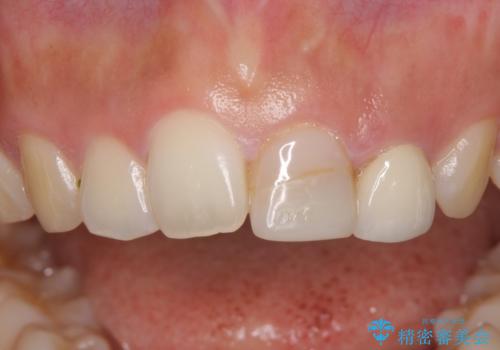

折れてしまって変色した前歯をオールセラミックに

- 中学生の時にスポーツで折ってしまった前歯が変色してしまったとのことで来院された患者様です。

結婚式に向けてオールセラミッククラウンにて仕上げていくこととしました。

既にクラウンが装着されていた歯は歯根の先端に病変が認められたため、根管治療を行うこととしました。